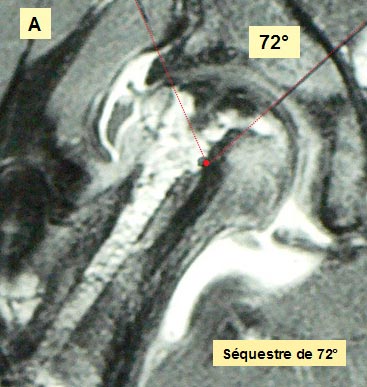

OSTEONECROSE SEVERE de la Hanche Droite Résection de la nécrose intra-céphalique Histoire Clinique Mlle M.N. est née le 23 juillet 1991. A l'âge de 14 ans, apparition d'une boiterie et de douleurs du genou gauche. Une Rx de la HG met en évidence une épiphysiolyse de grade 2. (45°). Un vissage bilatéral est pratiqué fin novembre 2004. Au début de février 2006, la hanche droite devient douloureuse et se bloque. Il s' agit d'une ONA. Aucune étiologie d'ordre médical n'est retrouvée. Le matériel est retiré quelques jours plus tard. Deux thérapeutiques sont évoquées : soit une greffe de moelle osseuse, soit une ostéotomie inter-trochantérienne. L'arthro-scanner de mars 2006 montre l'aplatissement de la tête fémorale, l'enfoncement de la partie portante nécrosée, la déformation en miroir du toit et un épanchement intra-articulaire de stade 3. L'IRM confirme la nécrose de grade III. Après entretiens avec les parents, il est décidé de pratiquer un nettoyage de la zone nécrotique suivi d'un comblement-greffe à l'aide d'un composite formé d'un biomatériau et de moelle osseuse. L'intervention a lieu en mai 2006. La hanche est mise en décharge avec deux CB. La reprise de l'appui est progressive en fonction de la tolérance clinique en respectant la règle de la non-douleur. La marche sans canne est autorisée en mars 2008. Nous verrons les résultats 22 mois après l'intervention.

Que se passe t'il à l'intérieur de l'os ? Clichés comparatifs intermédiaires - A : L'IRMN avant la greffe de biomatériau montre l'étendue de la nécrose sur la hanche de face. - B : L'IRMN postopératoire à 10 mois précise l'étendue de la nécrose dans la tête fémorale « in situ ». - C : Les Rx standards pré et postopératoire à 16 mois précisent l'évolution de la nécrose. - D : Les Rx standards post - opératoire à J + 1 et à 16 mois précisent l'évolution du biomatériau. ETENDUE de la NÉCROSE

EVOLUTION de la NÉCROSE

MESURE DE LA SURFACE